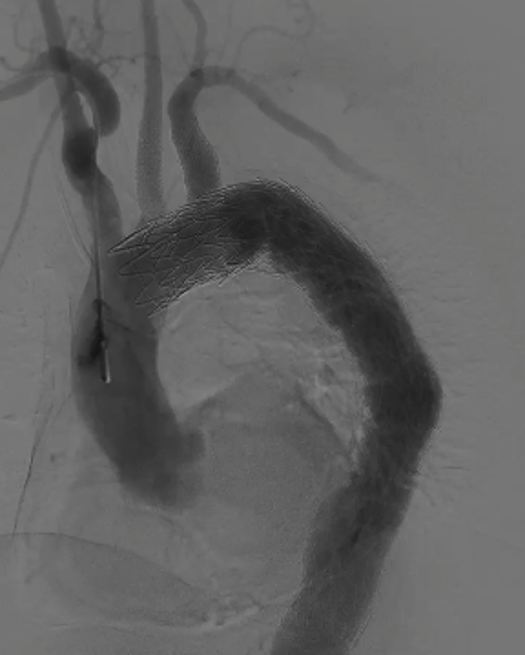

① 临时内漏技术

通过右肱动脉置入球囊,术中制造临时性Ⅰ型内漏,实现头臂干血流70%、左颈总动脉60%、左锁骨下动脉40%-50%的维持。

意义:无需依赖体外转流,简化操作,缩短手术时间,且数据支持其有效性(该技术已通过10例临床验证并在欧洲血管外科杂志发表,适用于各类开窗术式)。